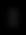

Representación de plano de aplicación con hilo canulado.

DISTANCIA DE LA DERMIS 3mm

Fuente: Ecografía realizada por la Dra. Cristiane Ribeiro - Radióloga y Dermatóloga